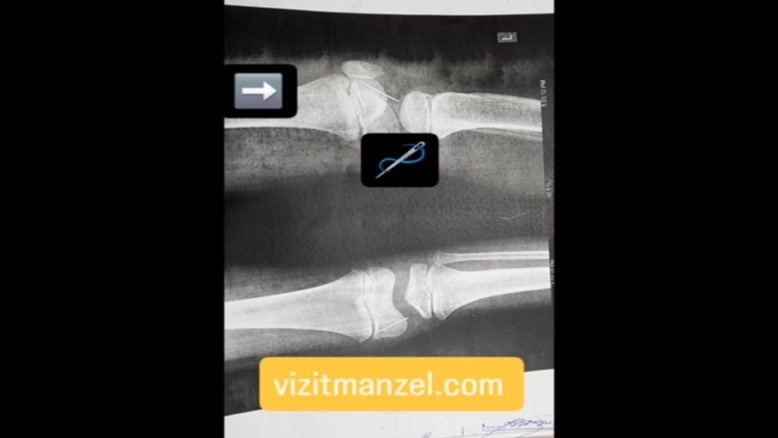

خارج کردن جسم خارجی توسط دکتر شاهدی

ویزیت در منزل 24 ساعته | خدمات پزشکی VIP با تعرفه مناسب